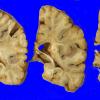

Subcortical Arteriosclerotic Encephalopathy (4)